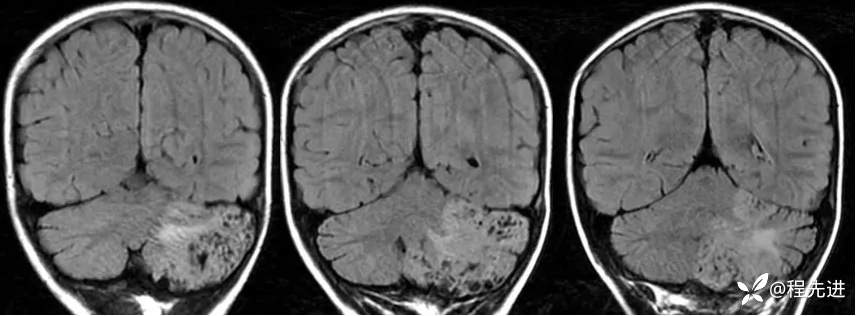

【患者信息】:男,6岁

【主诉】:查体发现左侧小脑半球占位3个月

【现病史及既往史】:患者3个月前因鼻塞至外院就诊,行头颅CT检查偶然发现颅内占位

【检查】